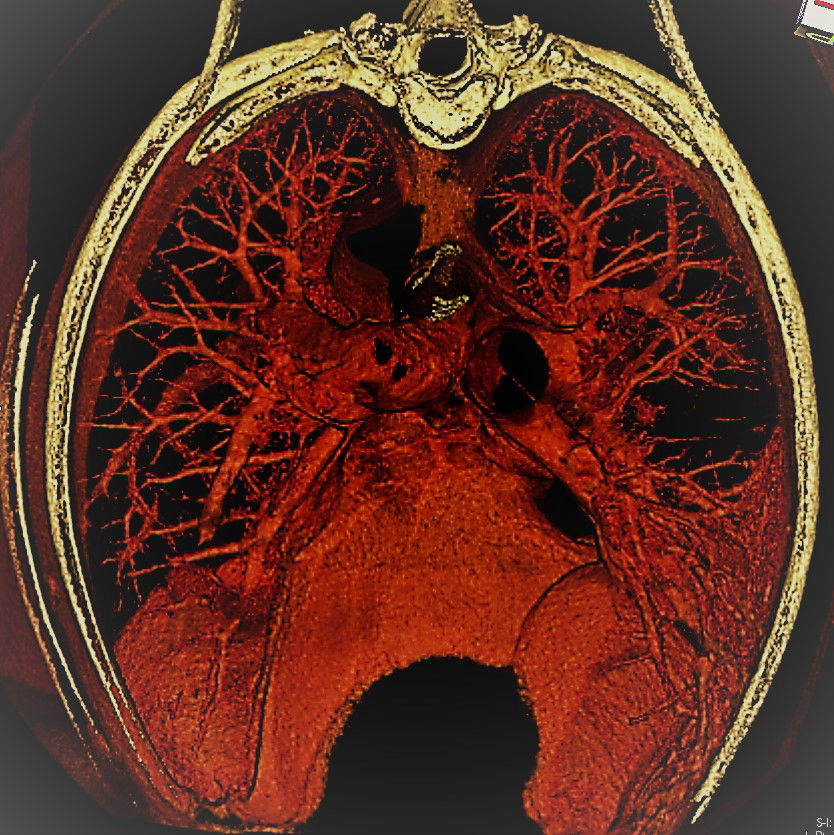

Canine Chest Reconstruction

3D Imaging

Our CT images are automatically reconstructed into 3D images to allow complete evaluation and the best possible diagnostic available for your pet.